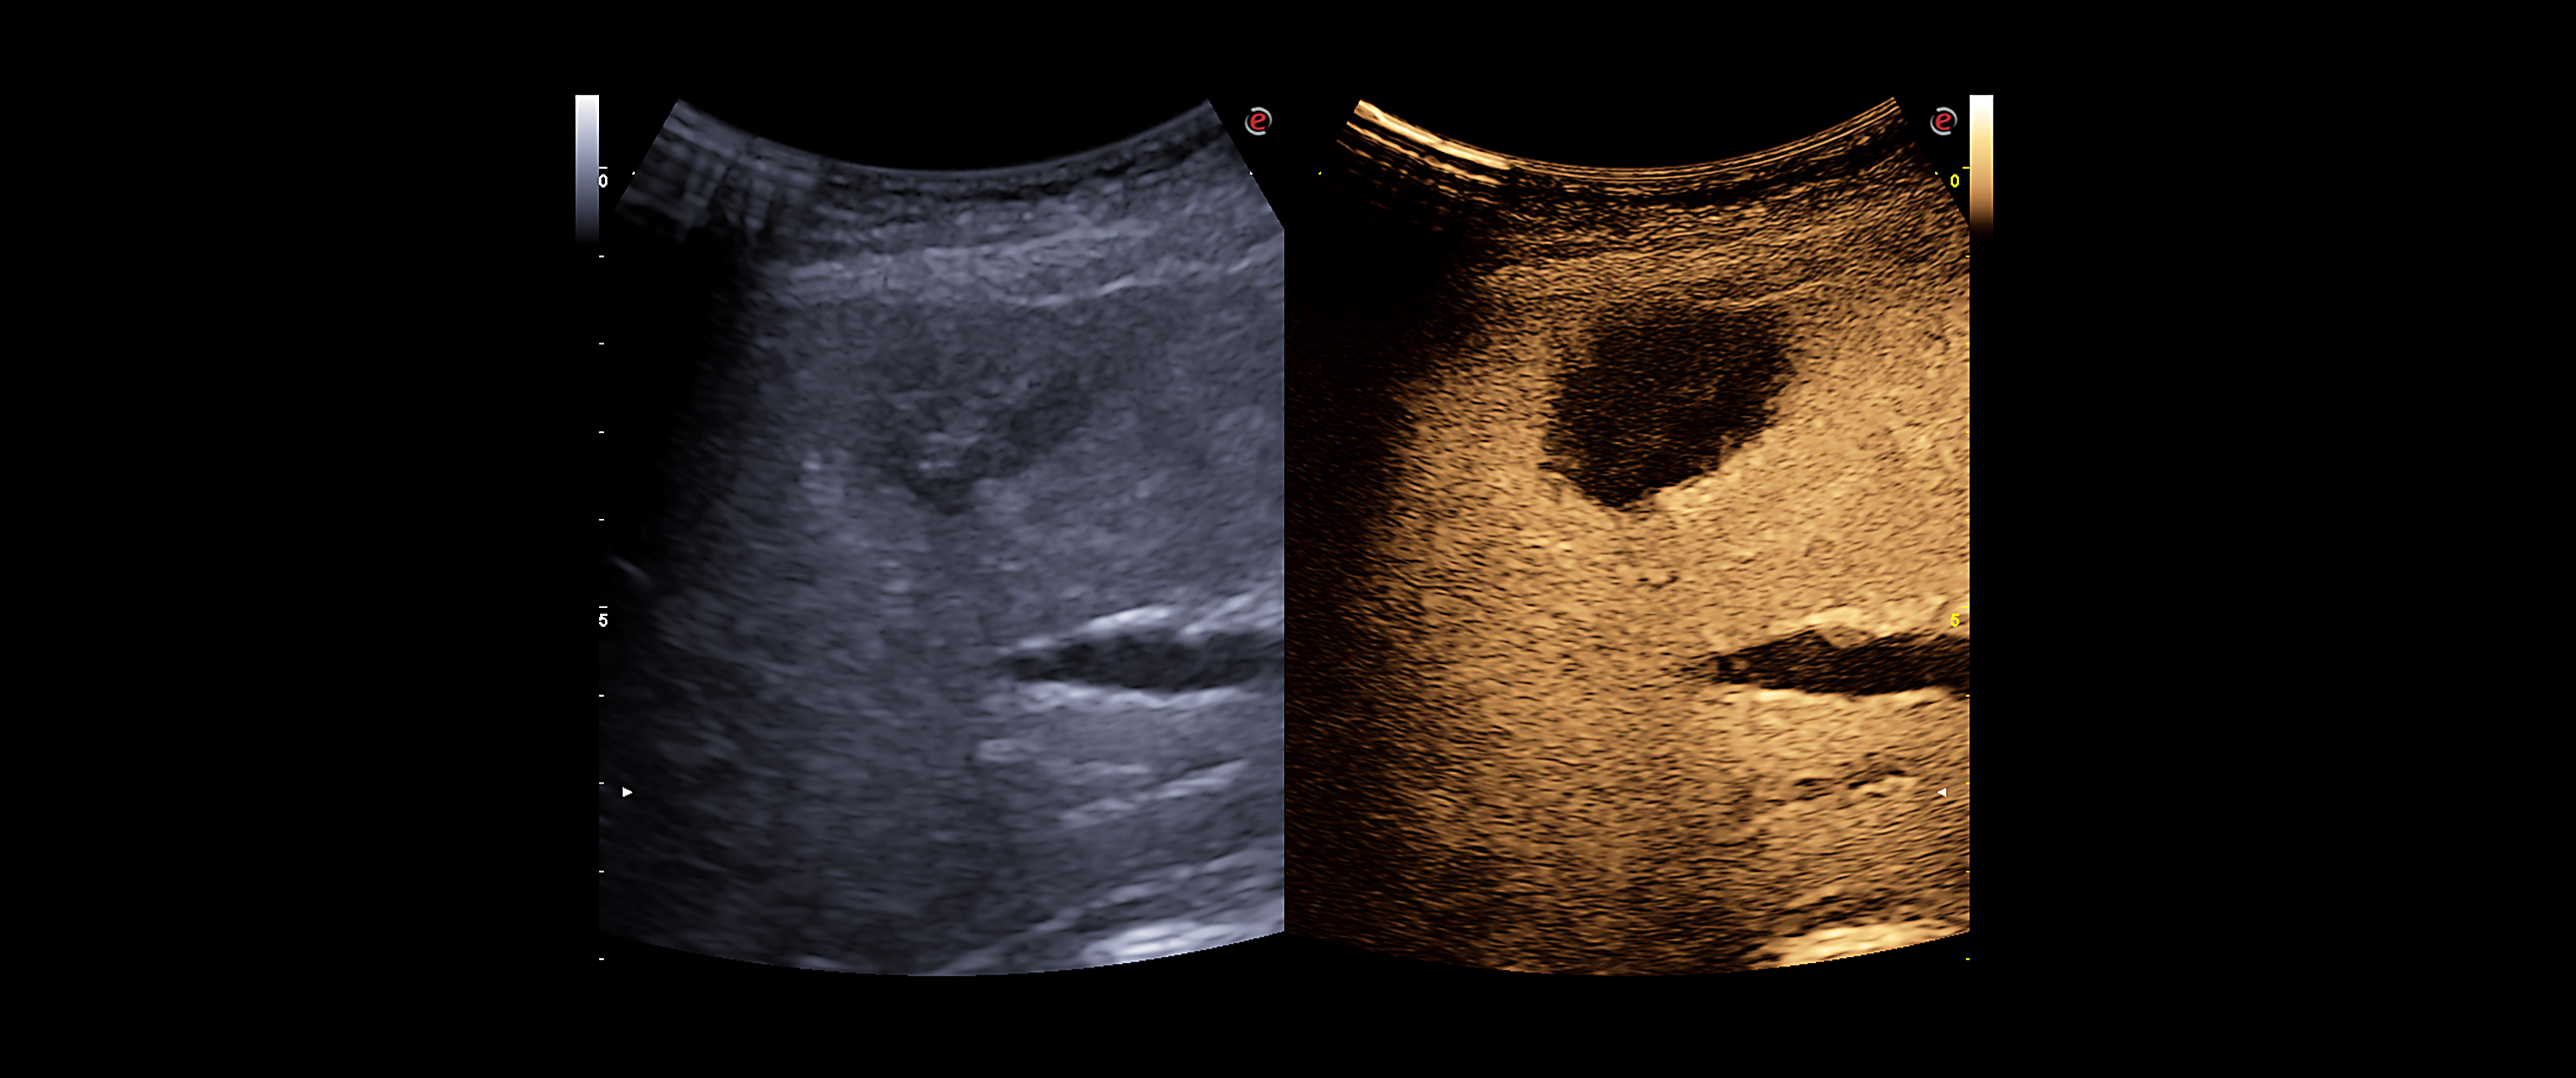

The characterisation of the lesions is essential in the global approach to follow-up and therapy options.

• microV: latest Esaote technology for microvascularisation visualisation with an elevated degree of sensitivity even in very small vessels and with slow flow detection. It enables advanced hemodynamic evaluation of lesions even in deep areas of the liver, thanks to exclusive filters that enhance only blood signals.

• CnTI™ Clear (Contrast Tuned Imaging): Contrast Enhanced Ultrasound (CEUS) Imaging of Esaote, CnTI™ Clear, detects organ perfusion through contrast agent enhancement to support liver and abdominal lesion characterisations. Based on cutting-edge software, CnTI™ Clear is able to detect low levels of microbubbles, especially in the early arterial phase, while it will ensure their longevity, to give you accurate information on how the lesion is reacting.